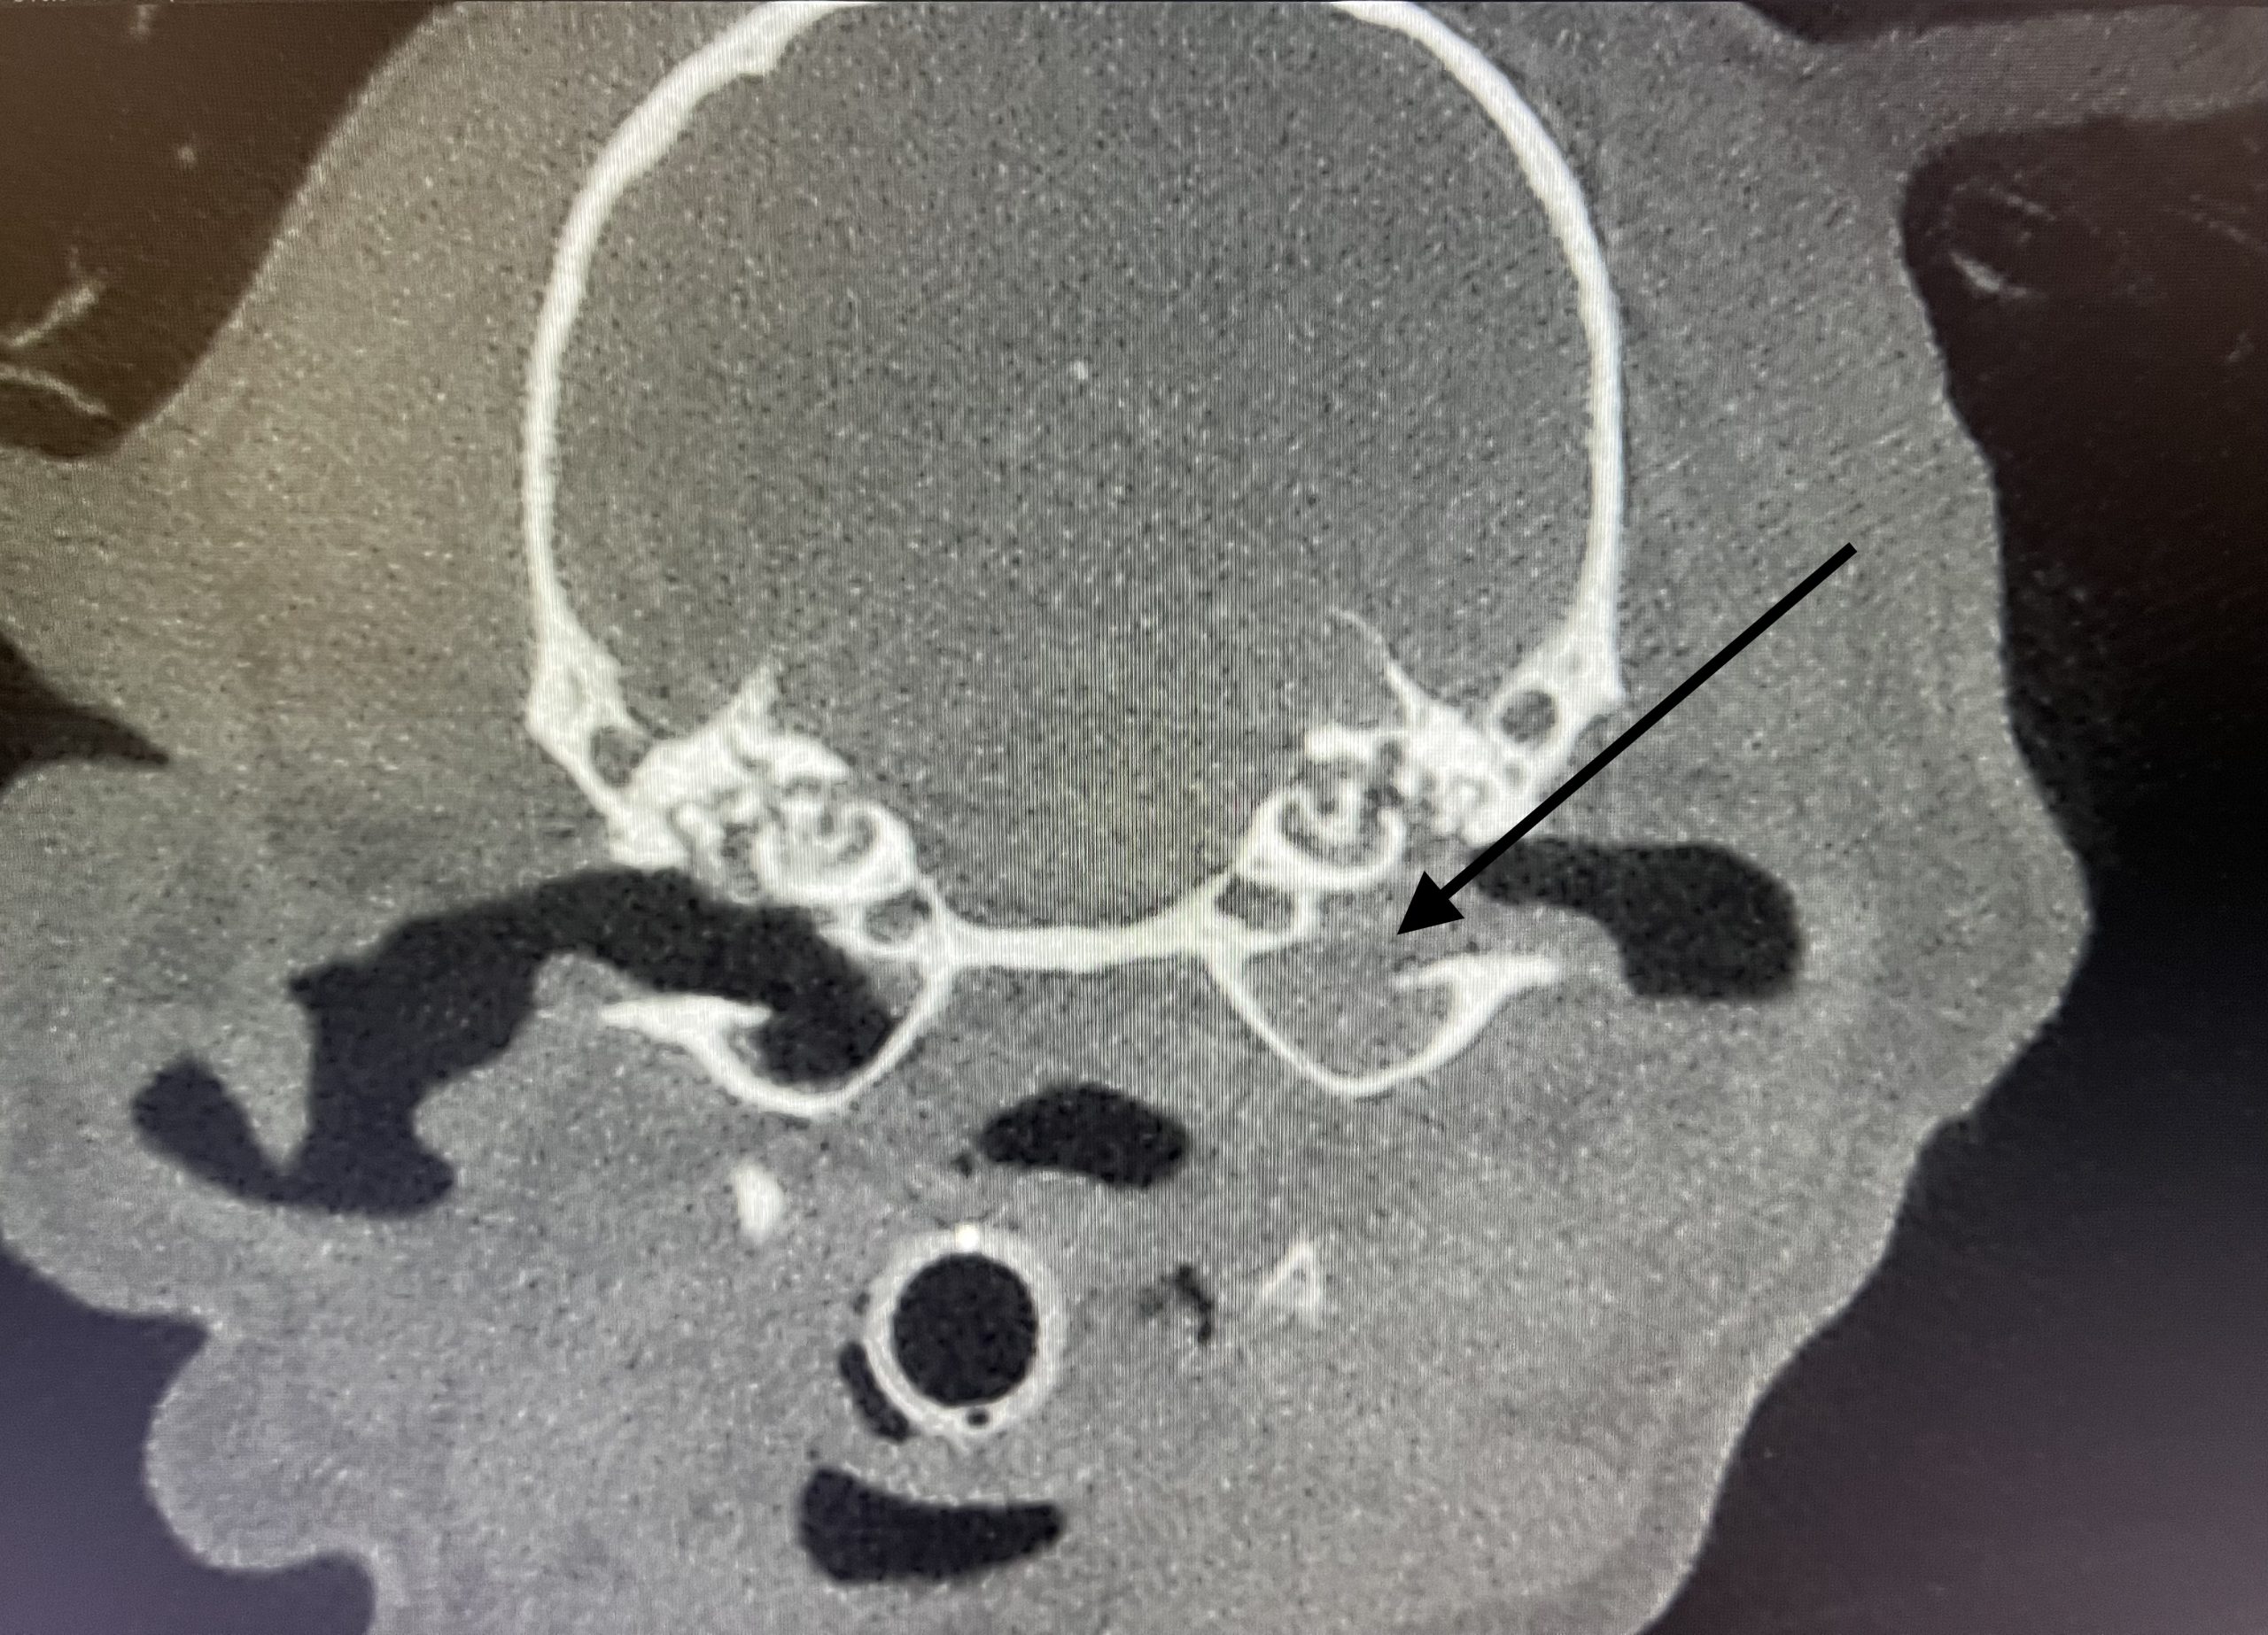

CBCT-röntgen (DT-röntgen) eller skiktröntgen är en avancerad röntgen som skapar 3-dimensionella bilder av skallen och mellanöronen. Utan denna diagnostik kan man inte se graden och omfattningen av förändringar i mellanörat. Vi har en så kallad CBCT (Verity Vet) som är en mindre CT lämpad just för denna diagnostik. Bildkvaliteten är mycket hög och ger detaljgranskning av de små vävnadsstrukturerna i örat. Vid CBCT räcker det att djuret får lugnande medicin. Scanningen tar inte mer än 40 sekunder. Vi läser av de flesta bilderna direkt men i vissa fall skickas de för extern granskning till radiolog (röntgenspecialist).

CT-röntgen (DT-röntgen) eller skiktröntgen är en avancerad röntgen som skapar 3-dimensionella bilder av skallen och mellanöronen. Utan denna diagnostik kan man inte se graden och omfattningen av förändringar i mellanörat. Vi har en så kallad CBCT (Verity Vet) som är en mindre CT lämpad just för denna diagnostik. Bildkvaliteten är mycket hög och ger detaljgranskning av de små vävnadsstrukturerna i örat. Vid CBCT räcker det att djuret får lugnande medicin. Scanningen tar inte mer än 40 sekunder. Vi läser av de flesta bilderna direkt men i vissa fall skickas de för extern granskning till radiolog (röntgenspecialist).

CBCT är en form av skiktröntgen (datortomografi) för skalle. Vid CBCT skapas 3D-bilder och man kan med hög skärpa se de små skelettdelarna som finns i mellanörat som hörselbenen eller trumhinnan.